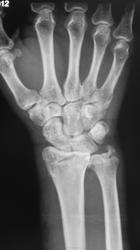

Сегодня был контроль, однако желаемое не достигнуто...

А "банкротом" может оказаться пациентка... Но это уже лирика)). Наше дело в данном случае маленькое: ДИНАМИКИ НЕТ, ВЫВИХ НЕ УСТРАНЕН. И всё))